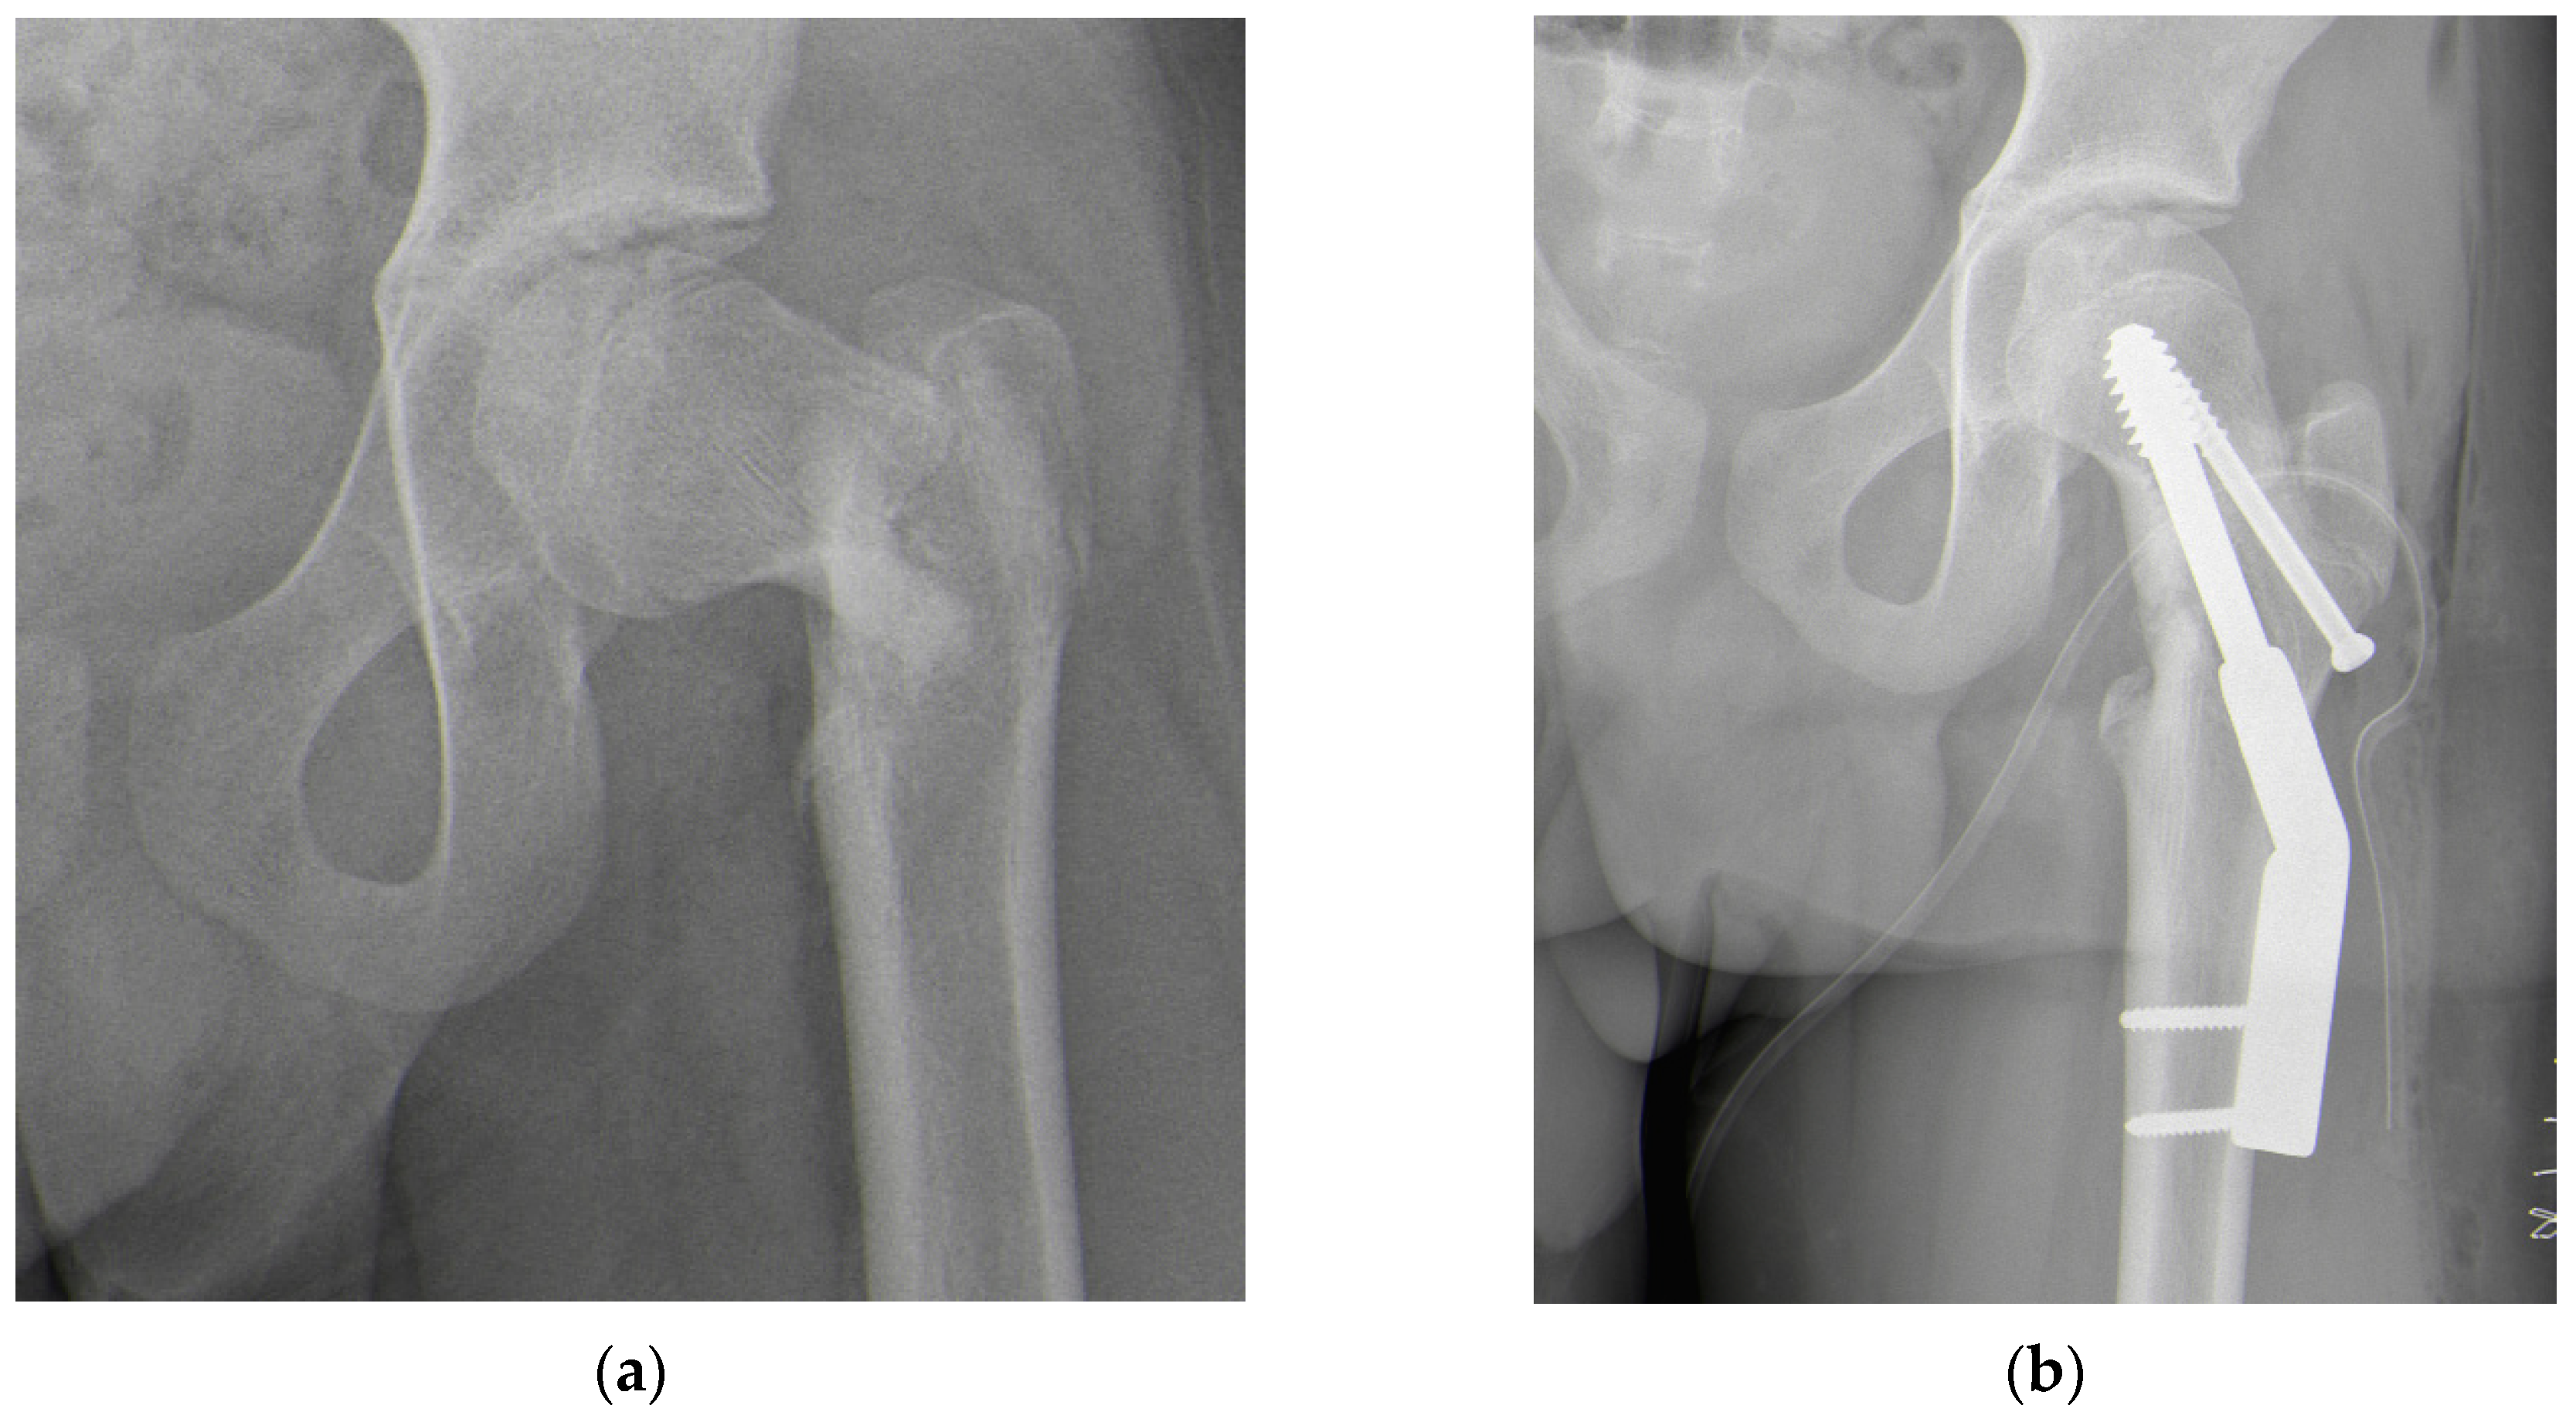

| Current study, 2024 | 15 | M | III | CR + plate | 1 | Severe | ISF + VFO + OChP |